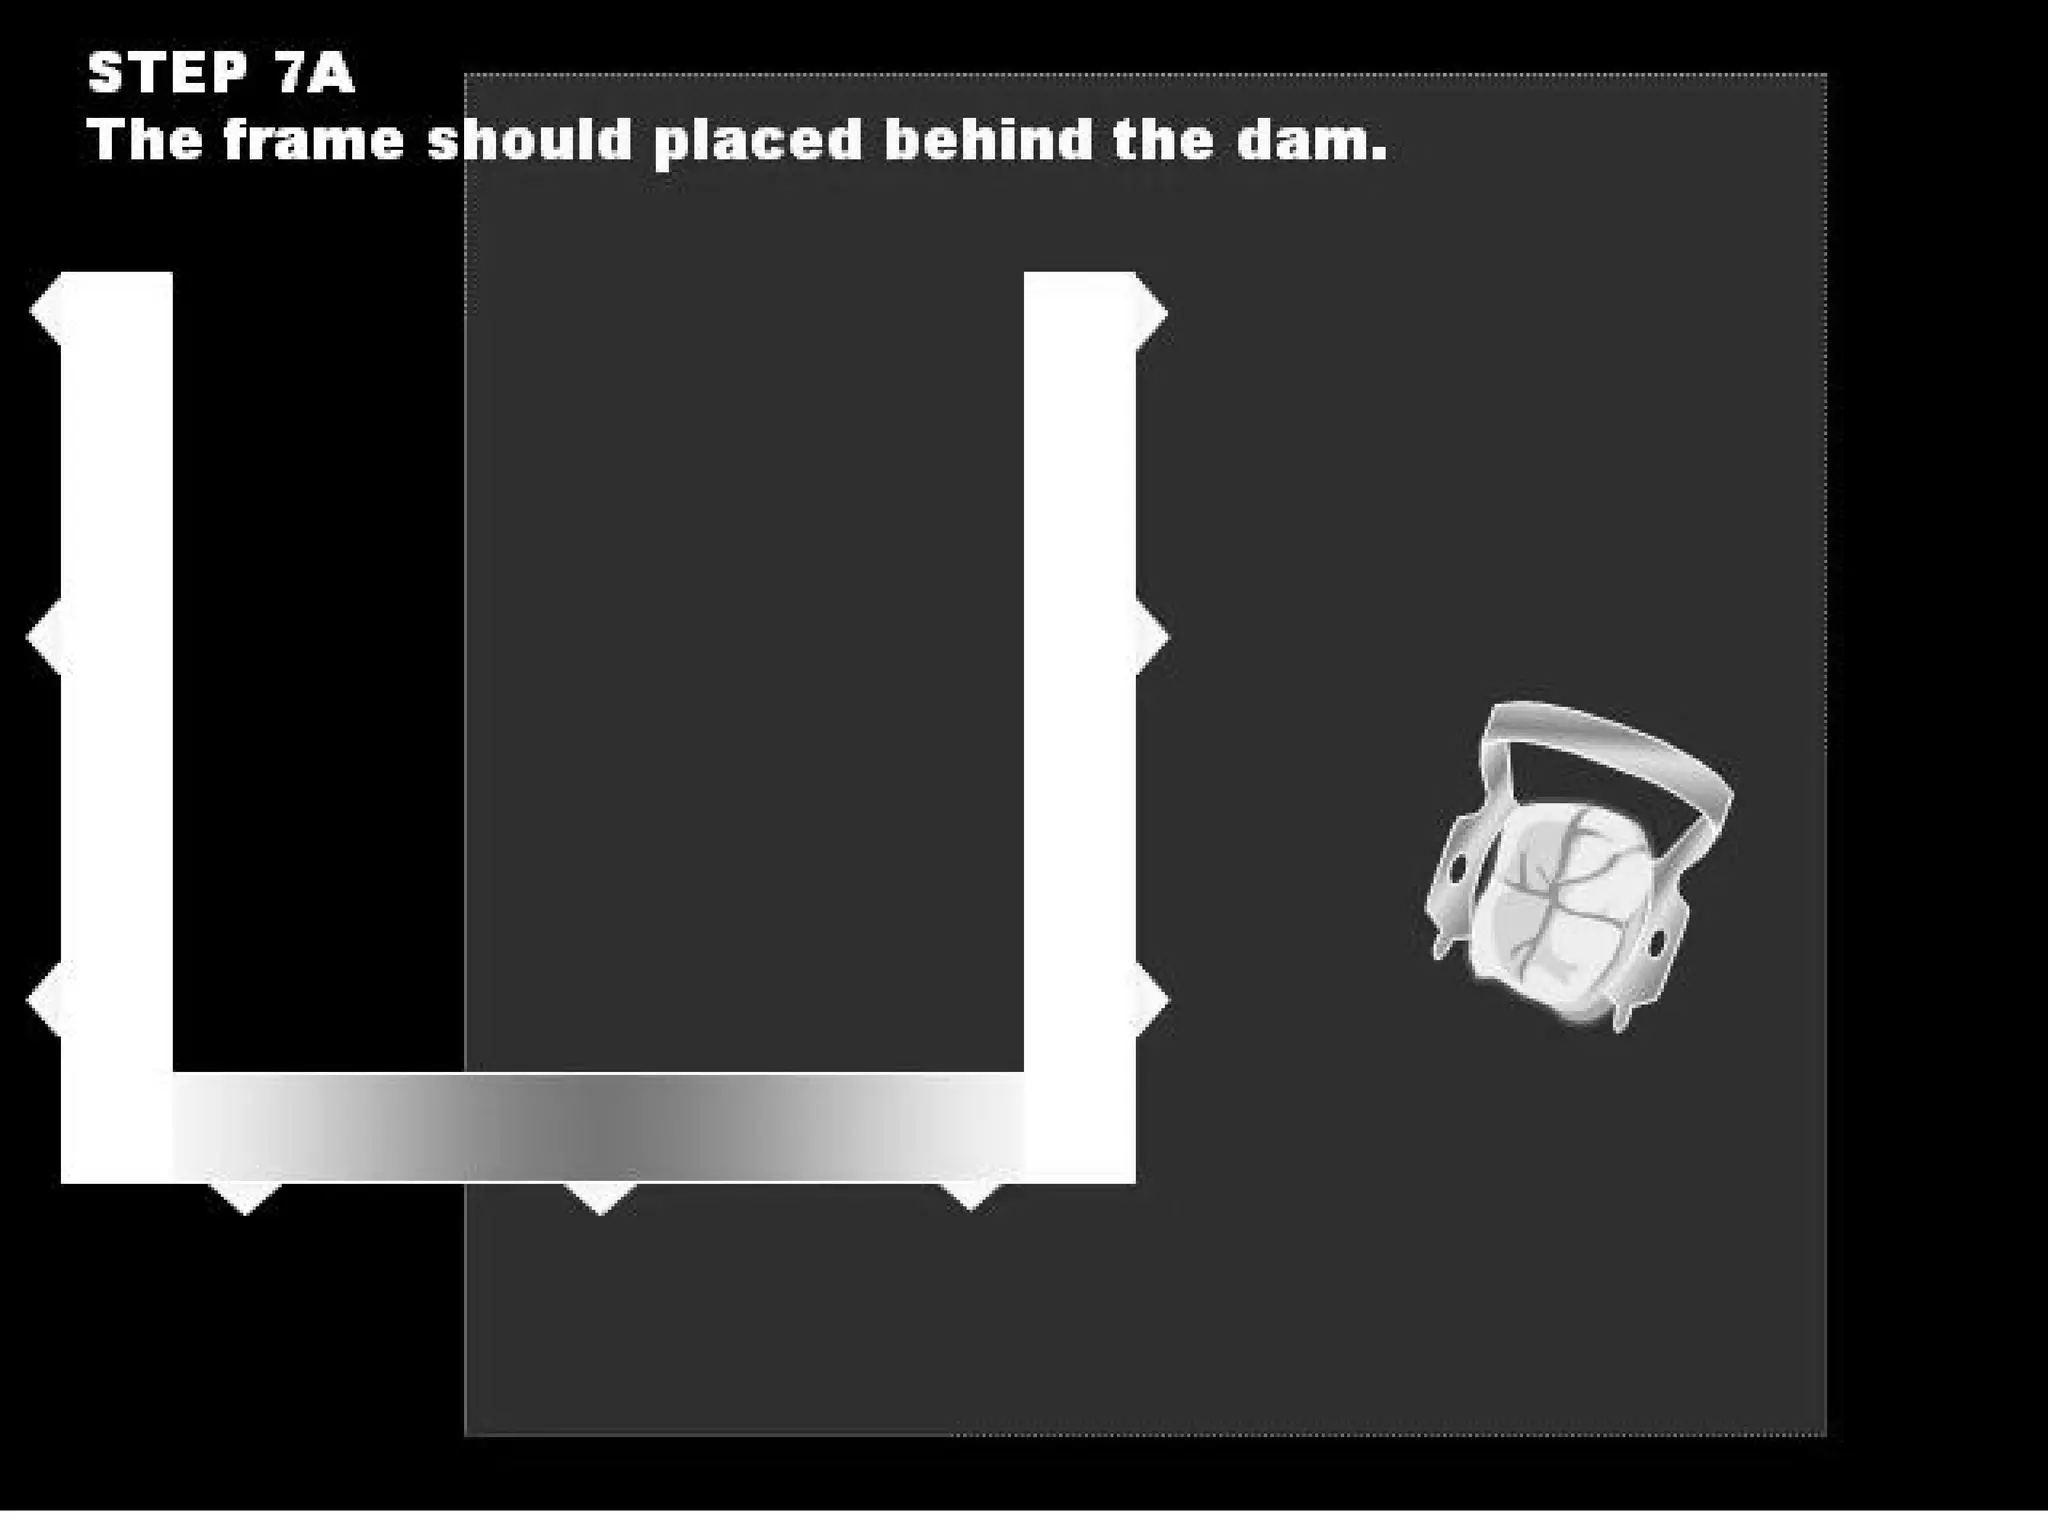

This document discusses the materials and components used for rubber dam isolation in dentistry. It describes the different types of rubber dam materials including color options and napkins to absorb moisture. It also outlines the tools needed such as punches to make holes, templates and stamps to guide hole placement, clamps to secure the dam, and other accessories like wedges and lubricant. Finally, it provides guidance on punching holes for different types of teeth and properly placing clamps in the rubber dam.